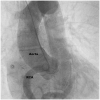

Case summary: We present a case of a 76-year-old patient with first presentation of ALCAPA. The coronary anomaly was first diagnosed during elective coronary angiography. The case was discussed at the Heart Team meeting and as the patient was asymptomatic, had good coronary collateral circulation, a medical treatment strategy was chosen and the patient was discharged in a good physical condition. During 3 years of follow-up, the patient has experienced no cardiovascular complications.